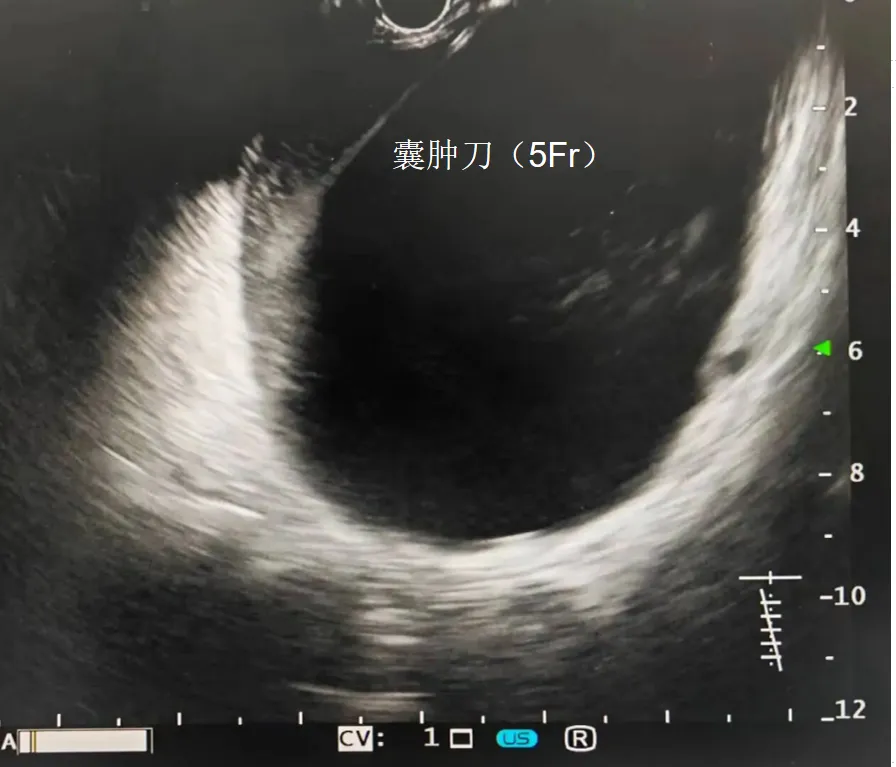

10Fr囊肿切开刀实际上相当于2把刀组装在一起,分别有2个连接的电极,5Fr的刀相当于内芯,10Fr的刀为外鞘,5Fr的电刀细软,进入囊肿碰到囊壁后会弯曲成袢,比较安全,进入囊腔后可起到类似导丝引导及支撑的作用,方便10Fr囊肿切开刀安全进入囊腔扩大瘘口。

2. 造瘘:5Fr电刀通电穿刺进入囊腔;10Fr电刀通电进入囊腔